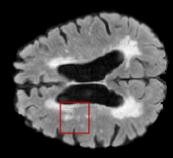

We evaluated our method in segmenting WMH from T1-w images using: a) Synthesized FLAIR images by treating the synthesis as a preprocessing step – we will refer to this method as offline synthesis; b) Synthesized FLAIR images using the proposed method, and c) without any synthesis – we will refer to this method as Unimodal. Baseline methods are illustrated in Figure 2

Table 2: Segmentation results for all proposed methods, each column represent a different slide in the image, blue areas are regions which were correctly labeled, false positives are shown in green, and false negatives in yellow

In order to better understand the above results, we visually analyzed the output segmentation performed for each method. Table 2 shows the results for three different slices (one slice per column). As illustrated, the proposed method is able to produce less false positives. It is also important to note that, unimodal segmentation is the one that produces more false positives, showing the advantage of using synthetic data. Regarding the nature of false positives, it can be easy to see in the third column a large number of false positives are on the border of periventricular lesions for the Unimodal method in comparison to the proposed method. Also from the first and second column, it can be observed that Unimodal tend to produce more small regions of false positives near to cortical areas. Removing such false positives requires additional post-processing steps, therefore, it is of value avoid this kind of over-segmentation. It can also be noted that synthesis methods tend to produce the same kind of false negatives, this may be due to the blurring effects in synthesized images since the information available during testing is limited – which otherwise is available from a FLAIR sequence.